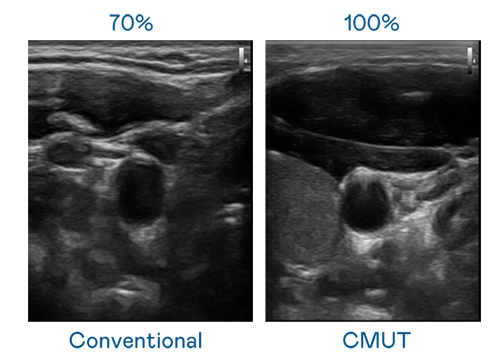

CMUT 技術是一種用電容式微機電元件來產生超音波訊號的技術。與傳統 PZT 壓電式技術相比,CMUT 頻寬增加 30%,更寬頻的超音波訊號讓影像解析度大幅提升,是實現高影像品質醫療超音波掃描、促進精準醫療發展的關鍵技術。

超音波影像的解析度高低,首先取決於探頭能發出的訊號頻寬。AG公司 CMUT 可提供高清晰的超音波訊號,提供高頻寬、高靈敏度、影像紋理細節更高的超音波影像,協助醫護人員縮短影像判讀時間及利用精準的醫療影像進行診斷。